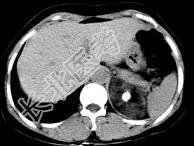

- 单项选择题男性,28岁, 左腰背酸胀5个月,CT检查如图所示, 应诊断为 ( )

A、左肾上腺髓样脂肪瘤

B、左肾上腺错构瘤

C、左肾上腺嗜铬细胞瘤

D、左肾上腺腺瘤

E、左肾上腺转移瘤